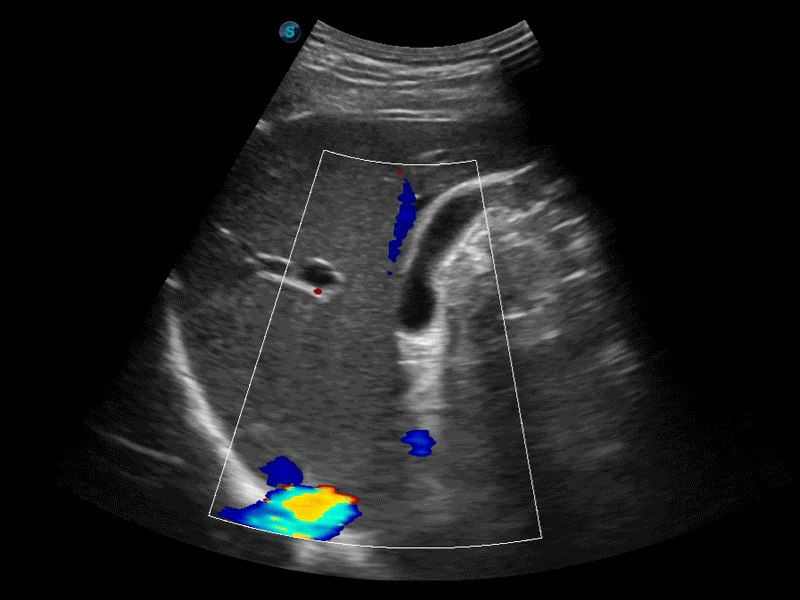

高分辨率血流成像技術提高了對低速血流信號的檢測能力。在提高空間分辨率的同時,也克服了血流外溢現(xiàn)象,為用戶提供更加真實的血流動力學信息。